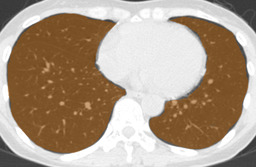

In this paper, we define partial annotation as an annotation format in which only one class is chosen for the annotation and only pixels belonging to the chosen class are annotated per image. For example, in Figure 1(a), although there is ground glass opacity in the image, only consolidation is chosen for annotation and pixels of consolidation are annotated. Partially annotated dataset is less informative for training, however, it is much easier to create compared to fully annotated dataset since annotators only need to focus on one class at a time during the annotation task.

Partially annotated datasets have been utilized previously [8, 9]. In this paper, we propose a new weak supervision technique that fully utilizes partially annotated dataset. Throughout this paper, each DLD pattern is represented or painted in the following colors (CON:cyan, GGO:yellow, HCM:red, EMP:green, NOR:brown.)

Statistics of our dataset are shown in Table 1 and typical images and their annotations for each DLD pattern are shown in Figure 1. In our partially annotated dataset, all the pixels in a slice were manually classified into two classes: dominating DLD pattern and other tissues. In other words, all the pixels in our dataset were assigned one of the labels from either of the two label sets, Lstrong={lCON,lGGO,lHCM,lEMP,lNOR}subscript𝐿𝑠𝑡𝑟𝑜𝑛𝑔subscript𝑙𝐶𝑂𝑁subscript𝑙𝐺𝐺𝑂subscript𝑙𝐻𝐶𝑀subscript𝑙𝐸𝑀𝑃subscript𝑙𝑁𝑂𝑅L_{strong}=\{l_{CON},l_{GGO},l_{HCM},l_{EMP},l_{NOR}\} or Lweak={lCON¯,lGGO¯,lHCM¯,lEMP¯,lNOR¯}subscript𝐿𝑤𝑒𝑎𝑘subscript𝑙¯𝐶𝑂𝑁subscript𝑙¯𝐺𝐺𝑂subscript𝑙¯𝐻𝐶𝑀subscript𝑙¯𝐸𝑀𝑃subscript𝑙¯𝑁𝑂𝑅L_{weak}=\{l_{\overline{CON}},l_{\overline{GGO}},l_{\overline{HCM}},l_{\overline{EMP}},l_{\overline{NOR}}\}. For example, in Figure 1(a), colored pixels were labeled as lCONsubscript𝑙𝐶𝑂𝑁l_{CON} and all the other pixels were labeled as lCON¯subscript𝑙¯𝐶𝑂𝑁l_{\overline{CON}}. In this paper, we call pixels of label lLweak𝑙subscript𝐿𝑤𝑒𝑎𝑘l\in L_{weak} and lLstrong𝑙subscript𝐿𝑠𝑡𝑟𝑜𝑛𝑔l\in L_{strong} as weakly annotated pixels and strongly annotated pixels respectively. Our pixel-wise annotations were created in the following steps. First, up to 3 slices were chosen for the annotation for each HRCT scan and for each slice, one representing DLD pattern was chosen by a radiologist. Second, three radiologists performed pixel-wise binary annotation (e.g. binary annotation between lCONsubscript𝑙𝐶𝑂𝑁l_{CON} or lCON¯subscript𝑙¯𝐶𝑂𝑁l_{\overline{CON}}) for each slice. Finally, the radiologists’ annotations were merged by taking majority classes for each pixel (i.e. pixels labeled as a DLD pattern by more than 2 radiologists became the corresponding DLD pixel). In addition to the DLDs annotation, lung fields were manually segmented under the supervision of radiologists and training and testing were conducted only within the lung fields.

Figure 1: Typical slices for each DLD classes. Slices of HRCT are shown in lung window setting (window-center=-600, window-width=1500) with annotated labels superimposed in transparent colors. Note that even if more than one DLD patterns existed, only one DLD pattern was chosen and annotated for a slice to facilitate the annotation process.